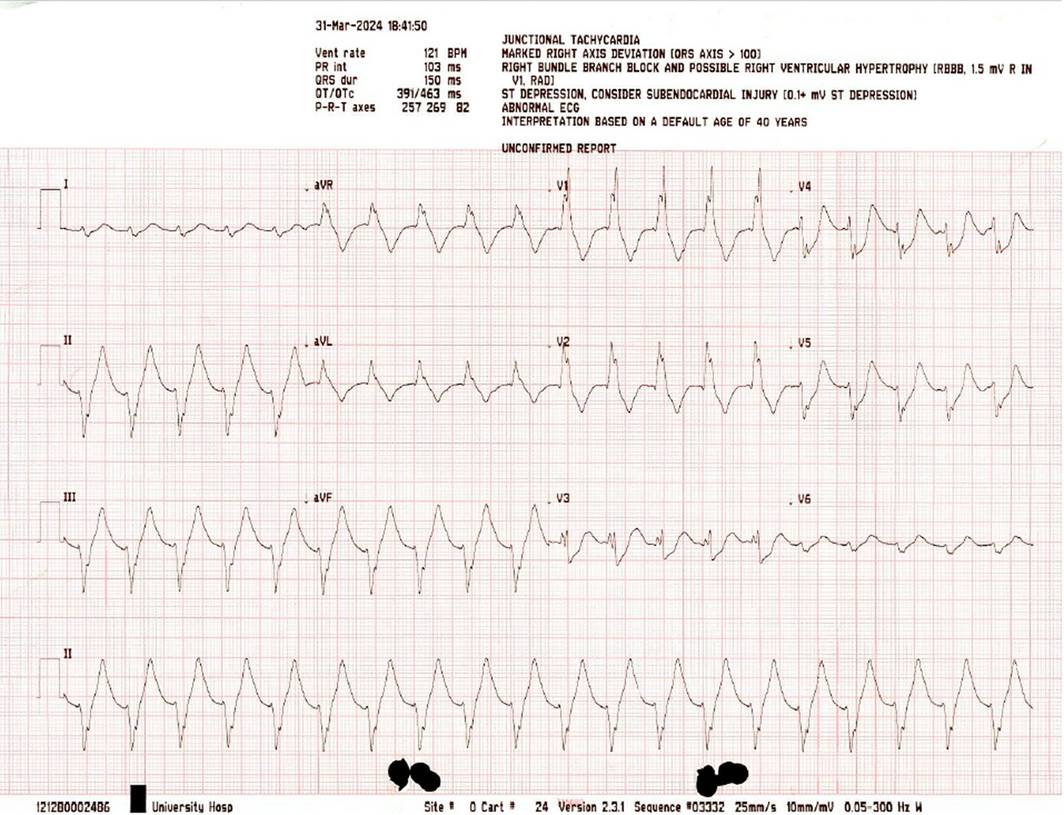

Box 2 – Electrocardiogram after the first return of spontaneous circulation

The patient underwent 19 minutes of cardiopulmonary resuscitation (CPR), including four defibrillator shocks of 200 J for ventricular fibrillation (Box 1) and pulseless ventricular tachycardia before return of spontaneous circulation (RoSC) of a broad complex tachycardia with palpable pulse (Box 2).